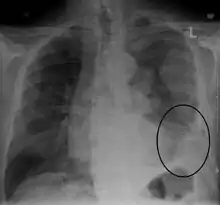

CXR demonstrating a mesothelioma